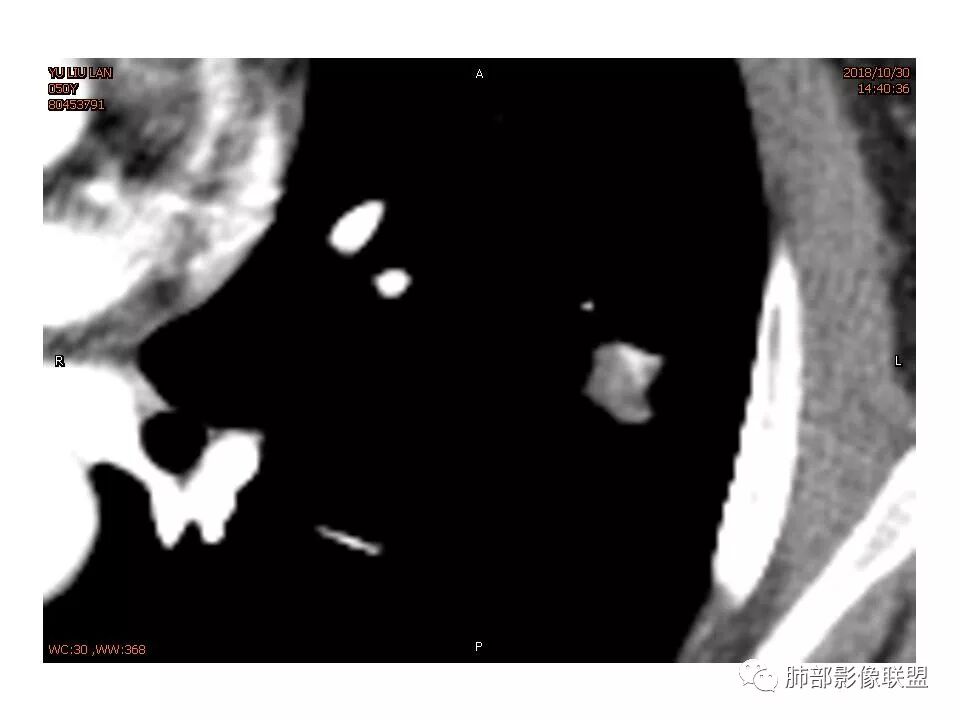

女,50。实性不规则结节,大小12*13mm,分叶、毛刺、胸膜凹陷,牵拉力强,增强渐进性强化,动脉期强化20,静脉期还有进一步强化。边缘强化,点状坏死。

其内血管被破坏。

女性,50岁。U型凹陷、平直征

南边:支持炎性

1.胸膜下略不规则实性密度结节影,孤立,缺乏典型深分叶,可见淡薄边界模糊磨玻璃晕,可见相对细长软毛刺。

2.如南边老师分析,病灶缺乏边缘膨隆优势,甚至部分平直内收。

3.病灶收缩力不强,整体强化程度不显著。

4.综上,病灶更符合炎性,如隐球菌感染等,而不大符合肺腺癌。具体到机化性肺炎略有些出乎预料。